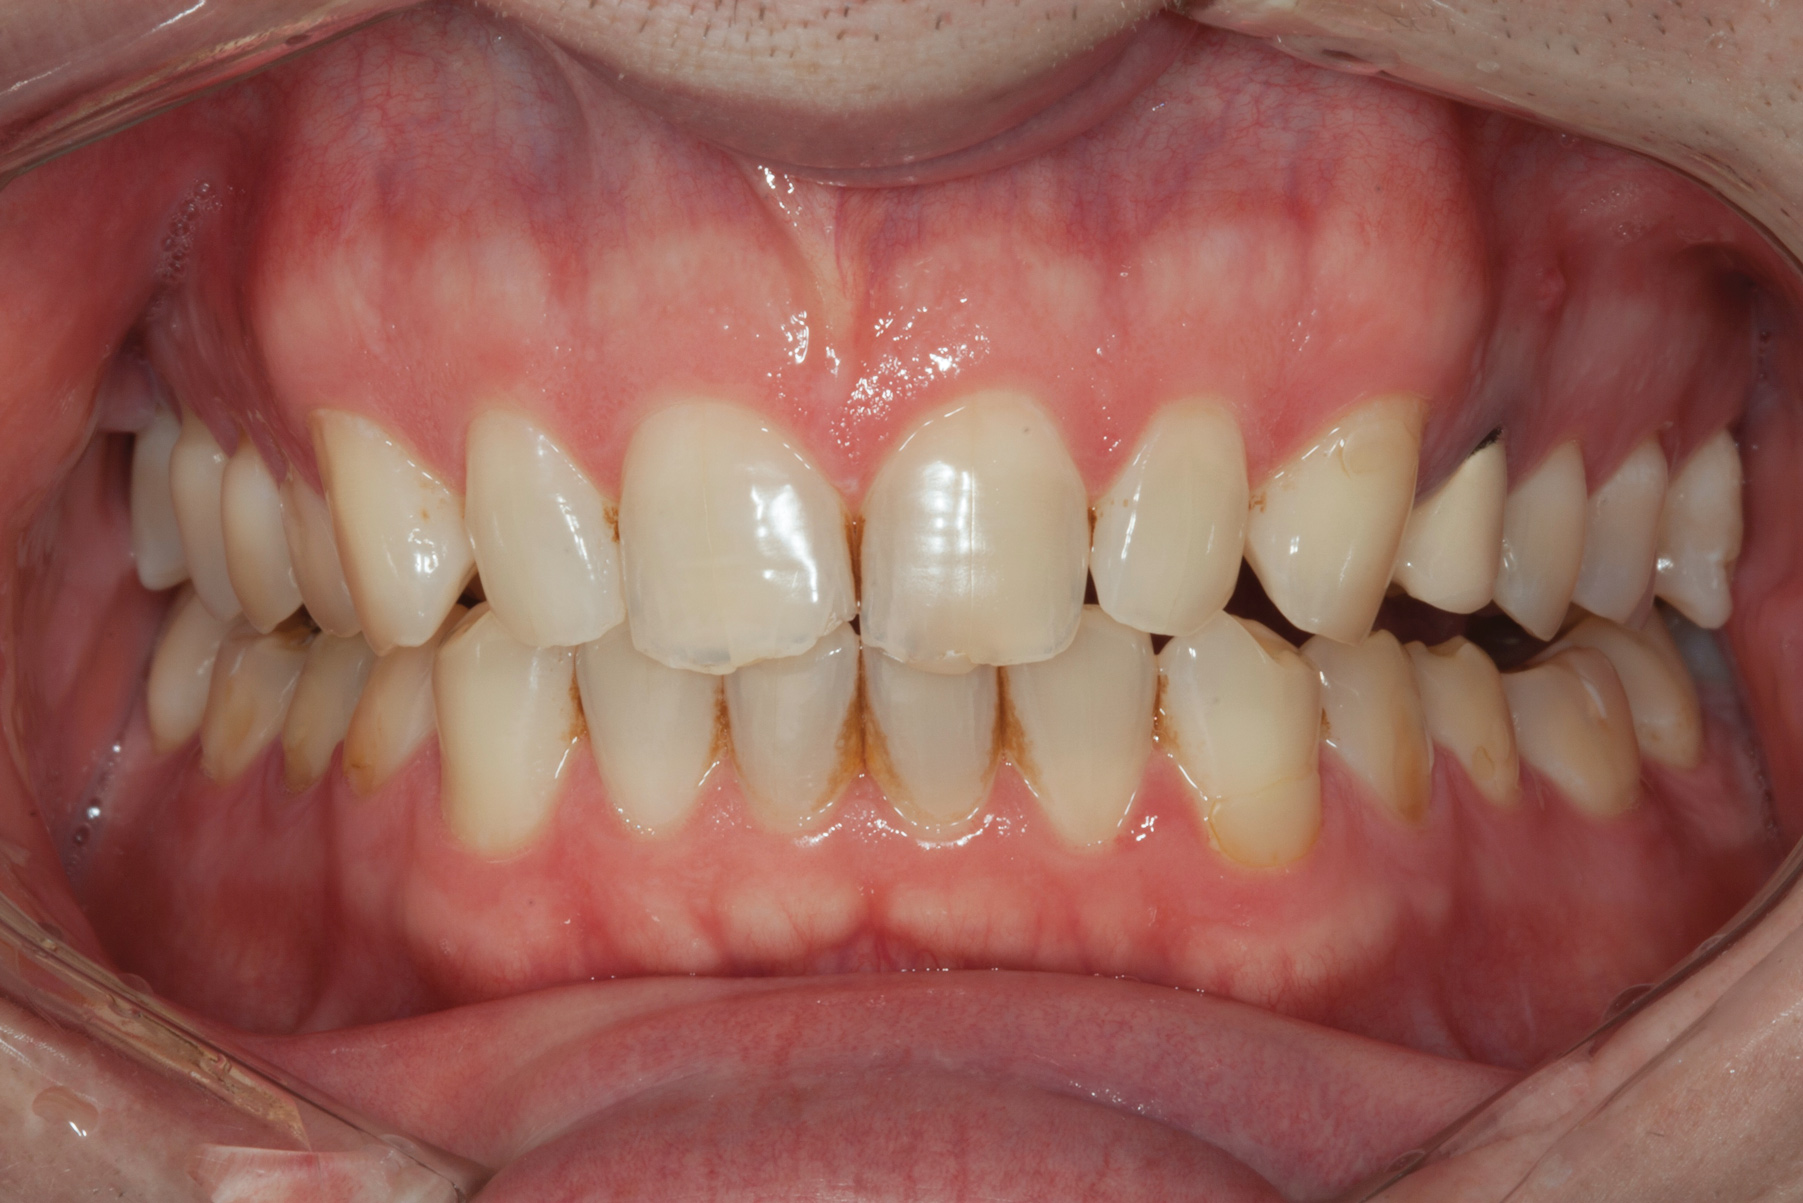

(2.) Preoperative retracted view.

Figure 2

A 34-year-old male patient with no medical issues presented to the office with the chief complaint of a failing crown on tooth No. 12. The patient was also unhappy with his bite and the appearance of his teeth (Figure 1 and Figure 2).

A comprehensive examination was carried out, and preoperative photographs were taken (Figure 1 through Figure 4). The patient presented with fair oral hygiene and slight, generalized tissue inflammation. Caries and defective restorations were detected on teeth Nos. 4, 5, 13, and 14. The crown on tooth No. 12 was showing signs of leakage, and although the endodontic access cavity had been temporarily restored with composite, this endodontic re-treatment was acceptable and the tooth was otherwise symptom-free. Erosion was present on most of the posterior teeth and the cuspids, and abrasion was noted on teeth Nos. 4, 5, 10, 11, 20, 21, 22, 28, and 29. An examination of the patient's muscles, joints, and bite revealed no joint sounds, a normal range of motion, and negative joint load and immobilization tests.

The dentofacial examination revealed a low smile line with no incisor display when the lips were in repose. The anterior teeth were chipped and worn, and their overall color was darkened. The buccal corridors were deficient, and the failing crown on tooth No. 12 was visible in a full smile.